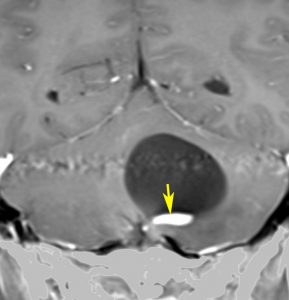

ものすごく難しい血管芽腫

これも血管芽腫です。おそらく小脳発生なのでしょうが,延髄の両側に強く癒着していて延髄の血管も腫瘍の中に入っていて,腫瘍血管には動脈瘤も合併していて破裂しました。この腫瘍を摘出するのは不可能にも思えましたが,無事にできました(下の写真)。患者さんも私もへとへとになりました。 でも,このような血管芽腫の手術はうまく行くとは限りません,手術不可能と考えた方がいいかもしれないと今でも思っています。手術すると決めればものすごく高いリスクを患者さんも外科医も背負うことになります。放射線治療をして治るサイズではないので他に治療法はありませんが (>_<) 大きな血管芽腫を手術する提案をされたら,少なくとも執刀医の経験数は尋ねましょう。